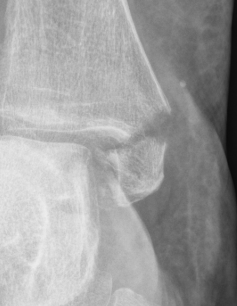

![]() |